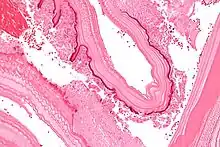

From the embryo released from an egg develops a hydatid cyst, which grows to about 5–10 cm within the first year and is able to survive within organs for years.[25] Cysts sometimes grow to be so large that by the end of several years or even decades, they can contain several liters of fluid. Once a cyst has reached a diameter of 1 cm, its wall differentiates into a thick outer, non-cellular membrane, which covers the thin germinal epithelium. From this epithelium, cells begin to grow within the cyst. These cells then become vacuolated, and are known as brood capsules, which are the parts of the parasite from which protoscolices bud. Often, daughter cysts also form within cysts.[24]